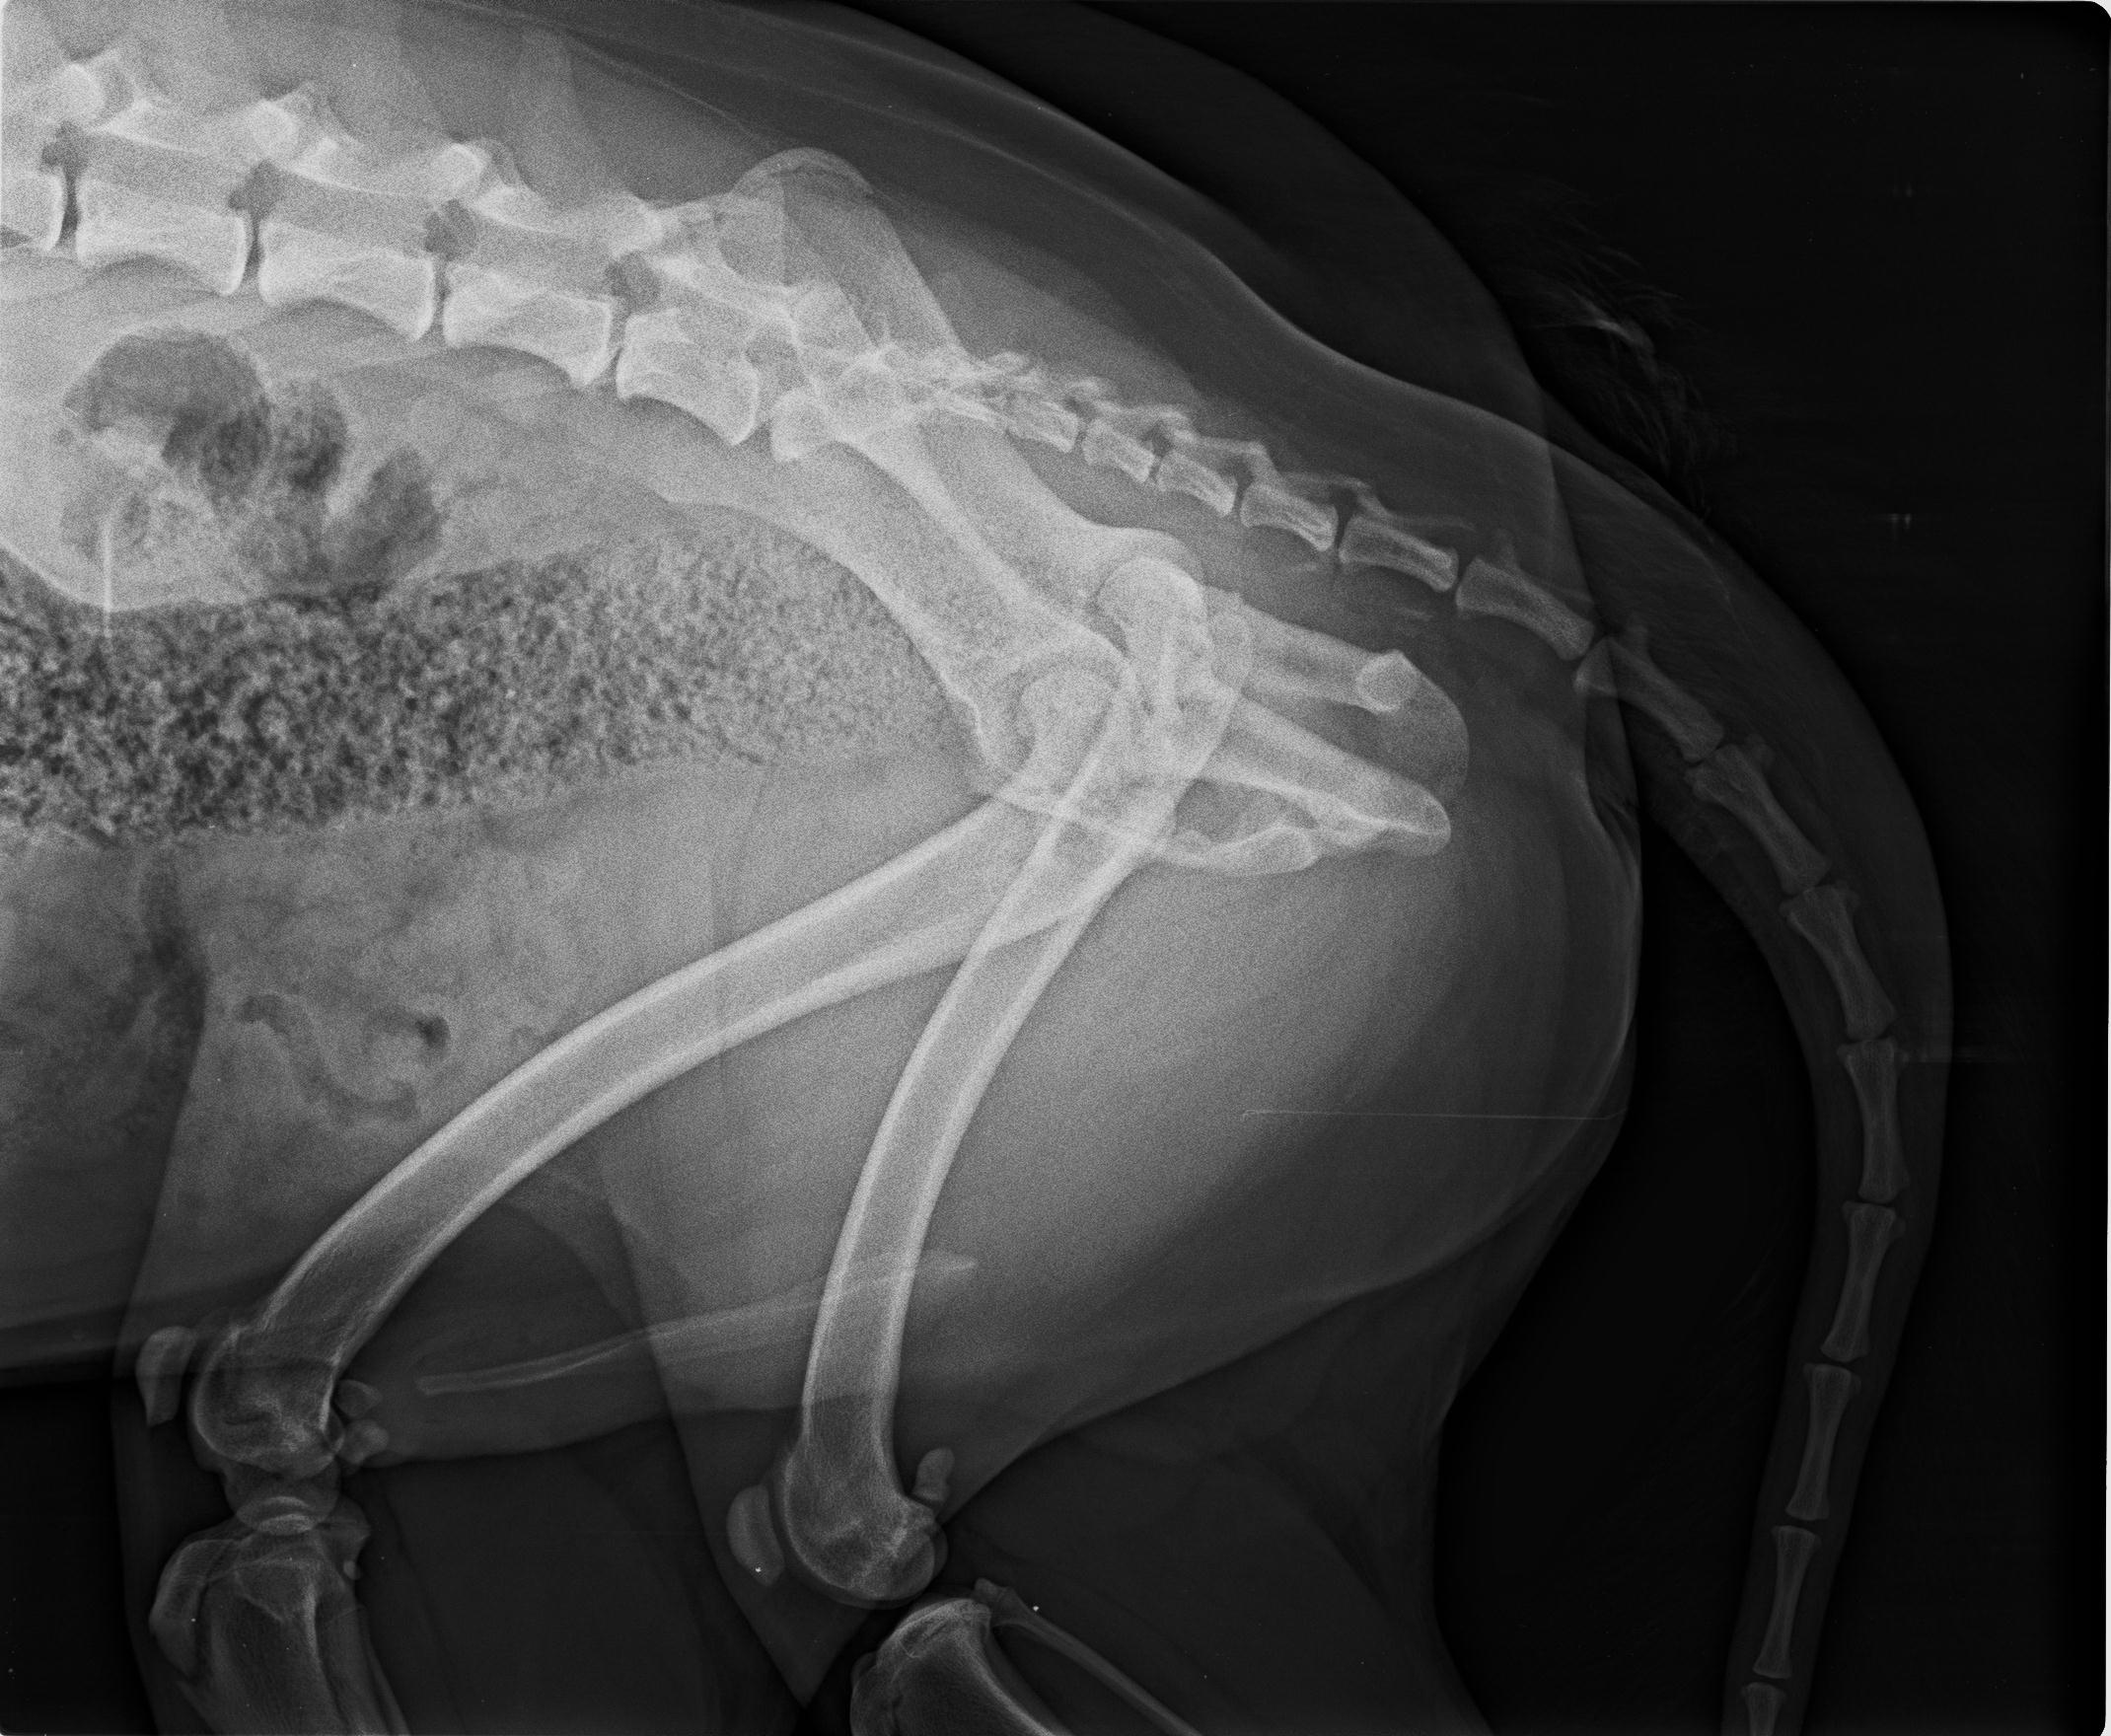

04.08.2025 neue Bilder, neues Video. Wir behandelten ihn mit Vitaminen und er schien sich gut zu entwickeln, er fing an, sich besser zu bewegen, obwohl wir mit der Zeit ein leichtes Hinken in seinem rechten Hinterbein bemerkten. Wir machten eine Röntgenaufnahme und der Tierarzt riet, den Oberschenkelkopf zu entfernen. Es dauerte viele Monate, bis er sich von der ersten Operation erholt hatte, so dass wir nicht wussten, ob wir auch das andere Bein operieren sollten. Aber dann begann Garfield, starke Schmerzen in seinem nicht operierten Bein zu haben. Wir gingen wieder zum Tierarzt und er wurde im Mai dieses Jahres an seinem zweiten Hinterbein operiert. Garfield ist ein Hund, der ein Zuhause mit einem großen Garten braucht, er ist kein Hund für Spaziergänge, da er sehr schnell müde wird. Vielleicht ist es eine Folge seiner Hinterbeinprobleme, als er ein Welpe war, deshalb sind seine Bedürfnisse anders als die anderer Hunde. Er wäre glücklich mit einem schönen, großen Garten, einer liebevollen und verständnisvollen Familie und viel Ruhe – mehr braucht Garfield nicht, um der glücklichste Hund der Welt zu sein.